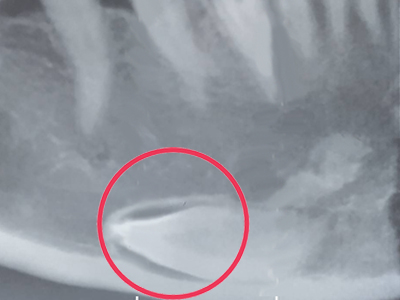

ภาพถ่าย x-ray แสดงฟันฝังในขากรรไกรล่างบริเวณคาง